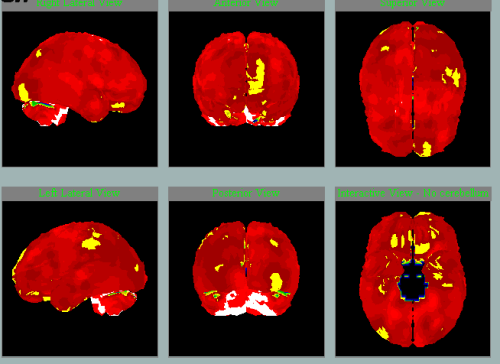

Takto na SPECT mozku zpracovaném NeuroGamem vypadá:

Normální perfúze

Perfúze při neurodegenerativním onemocnění mozku